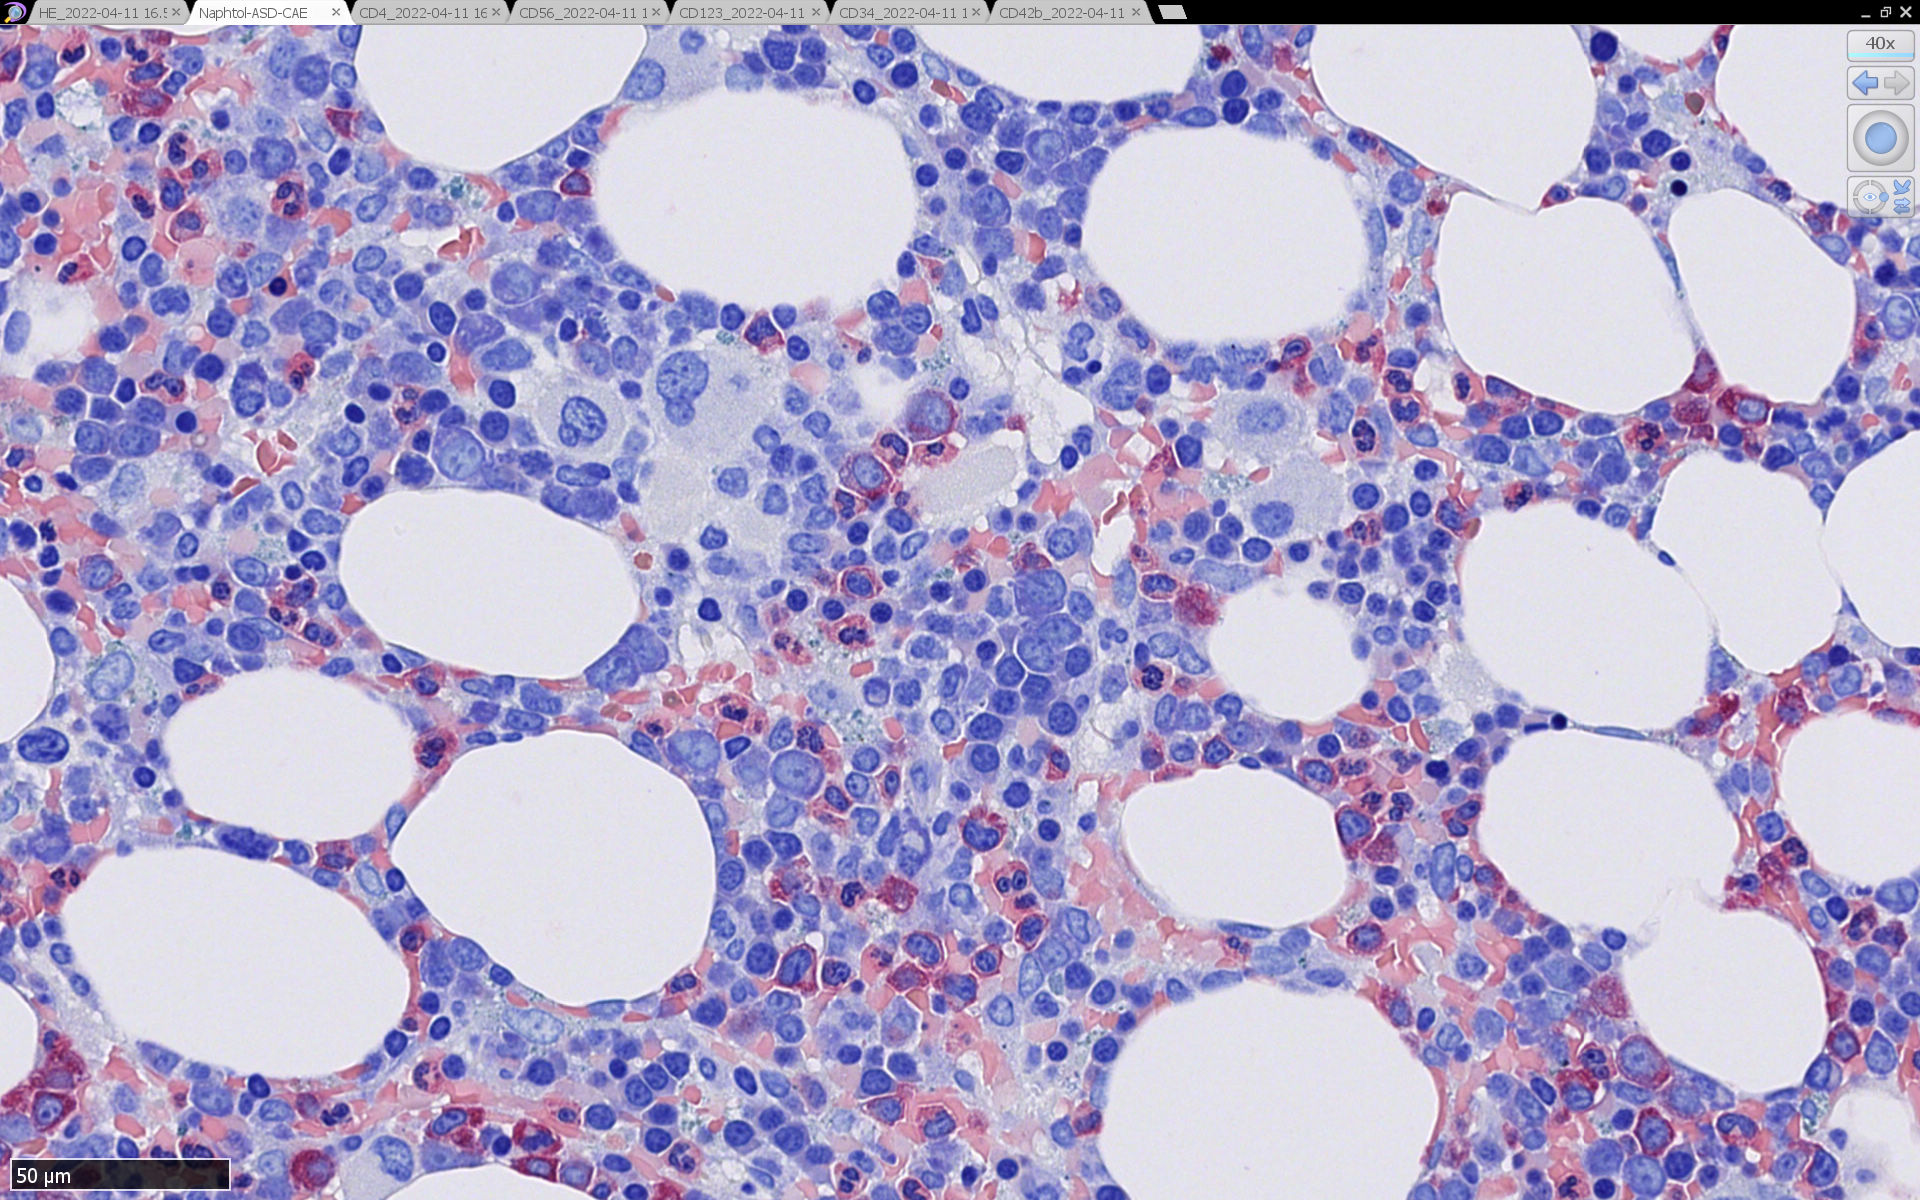

組織, 細胞病理

症例  画像サムネイルはクリックして大きな画像が見られます.

皮膚病変

blasticという名前から「大型細胞」を想起するが, この症例のようなclassical typeの細胞は思ったほど大きくはない. CD123陰性リンパ球とくらべてもあまり大きくないことがわかる.(散在する大型細胞はlysozyme+)

形態は均一で多型はめだたない.

腫瘍細胞は真皮を主座として, 皮下脂肪織まで, びまん性かつ単調monotonousに増殖することが多く, 表皮向性はみられない. 本例では血管や付属器中心あるいは脂肪織内に結節状の浸潤増殖を示した.

骨髄病理所見

HEでは腫瘍細胞の同定が難しい. 本症例は ASD-Giemsa染色を見ても, 腫瘍胞巣はよくわからなかった. 皮膚が先に診断がつき, 次いでBone marrowだったため, 免疫染色にすすめたが, Bone marrowが先だと診断に困ったかもしれない.